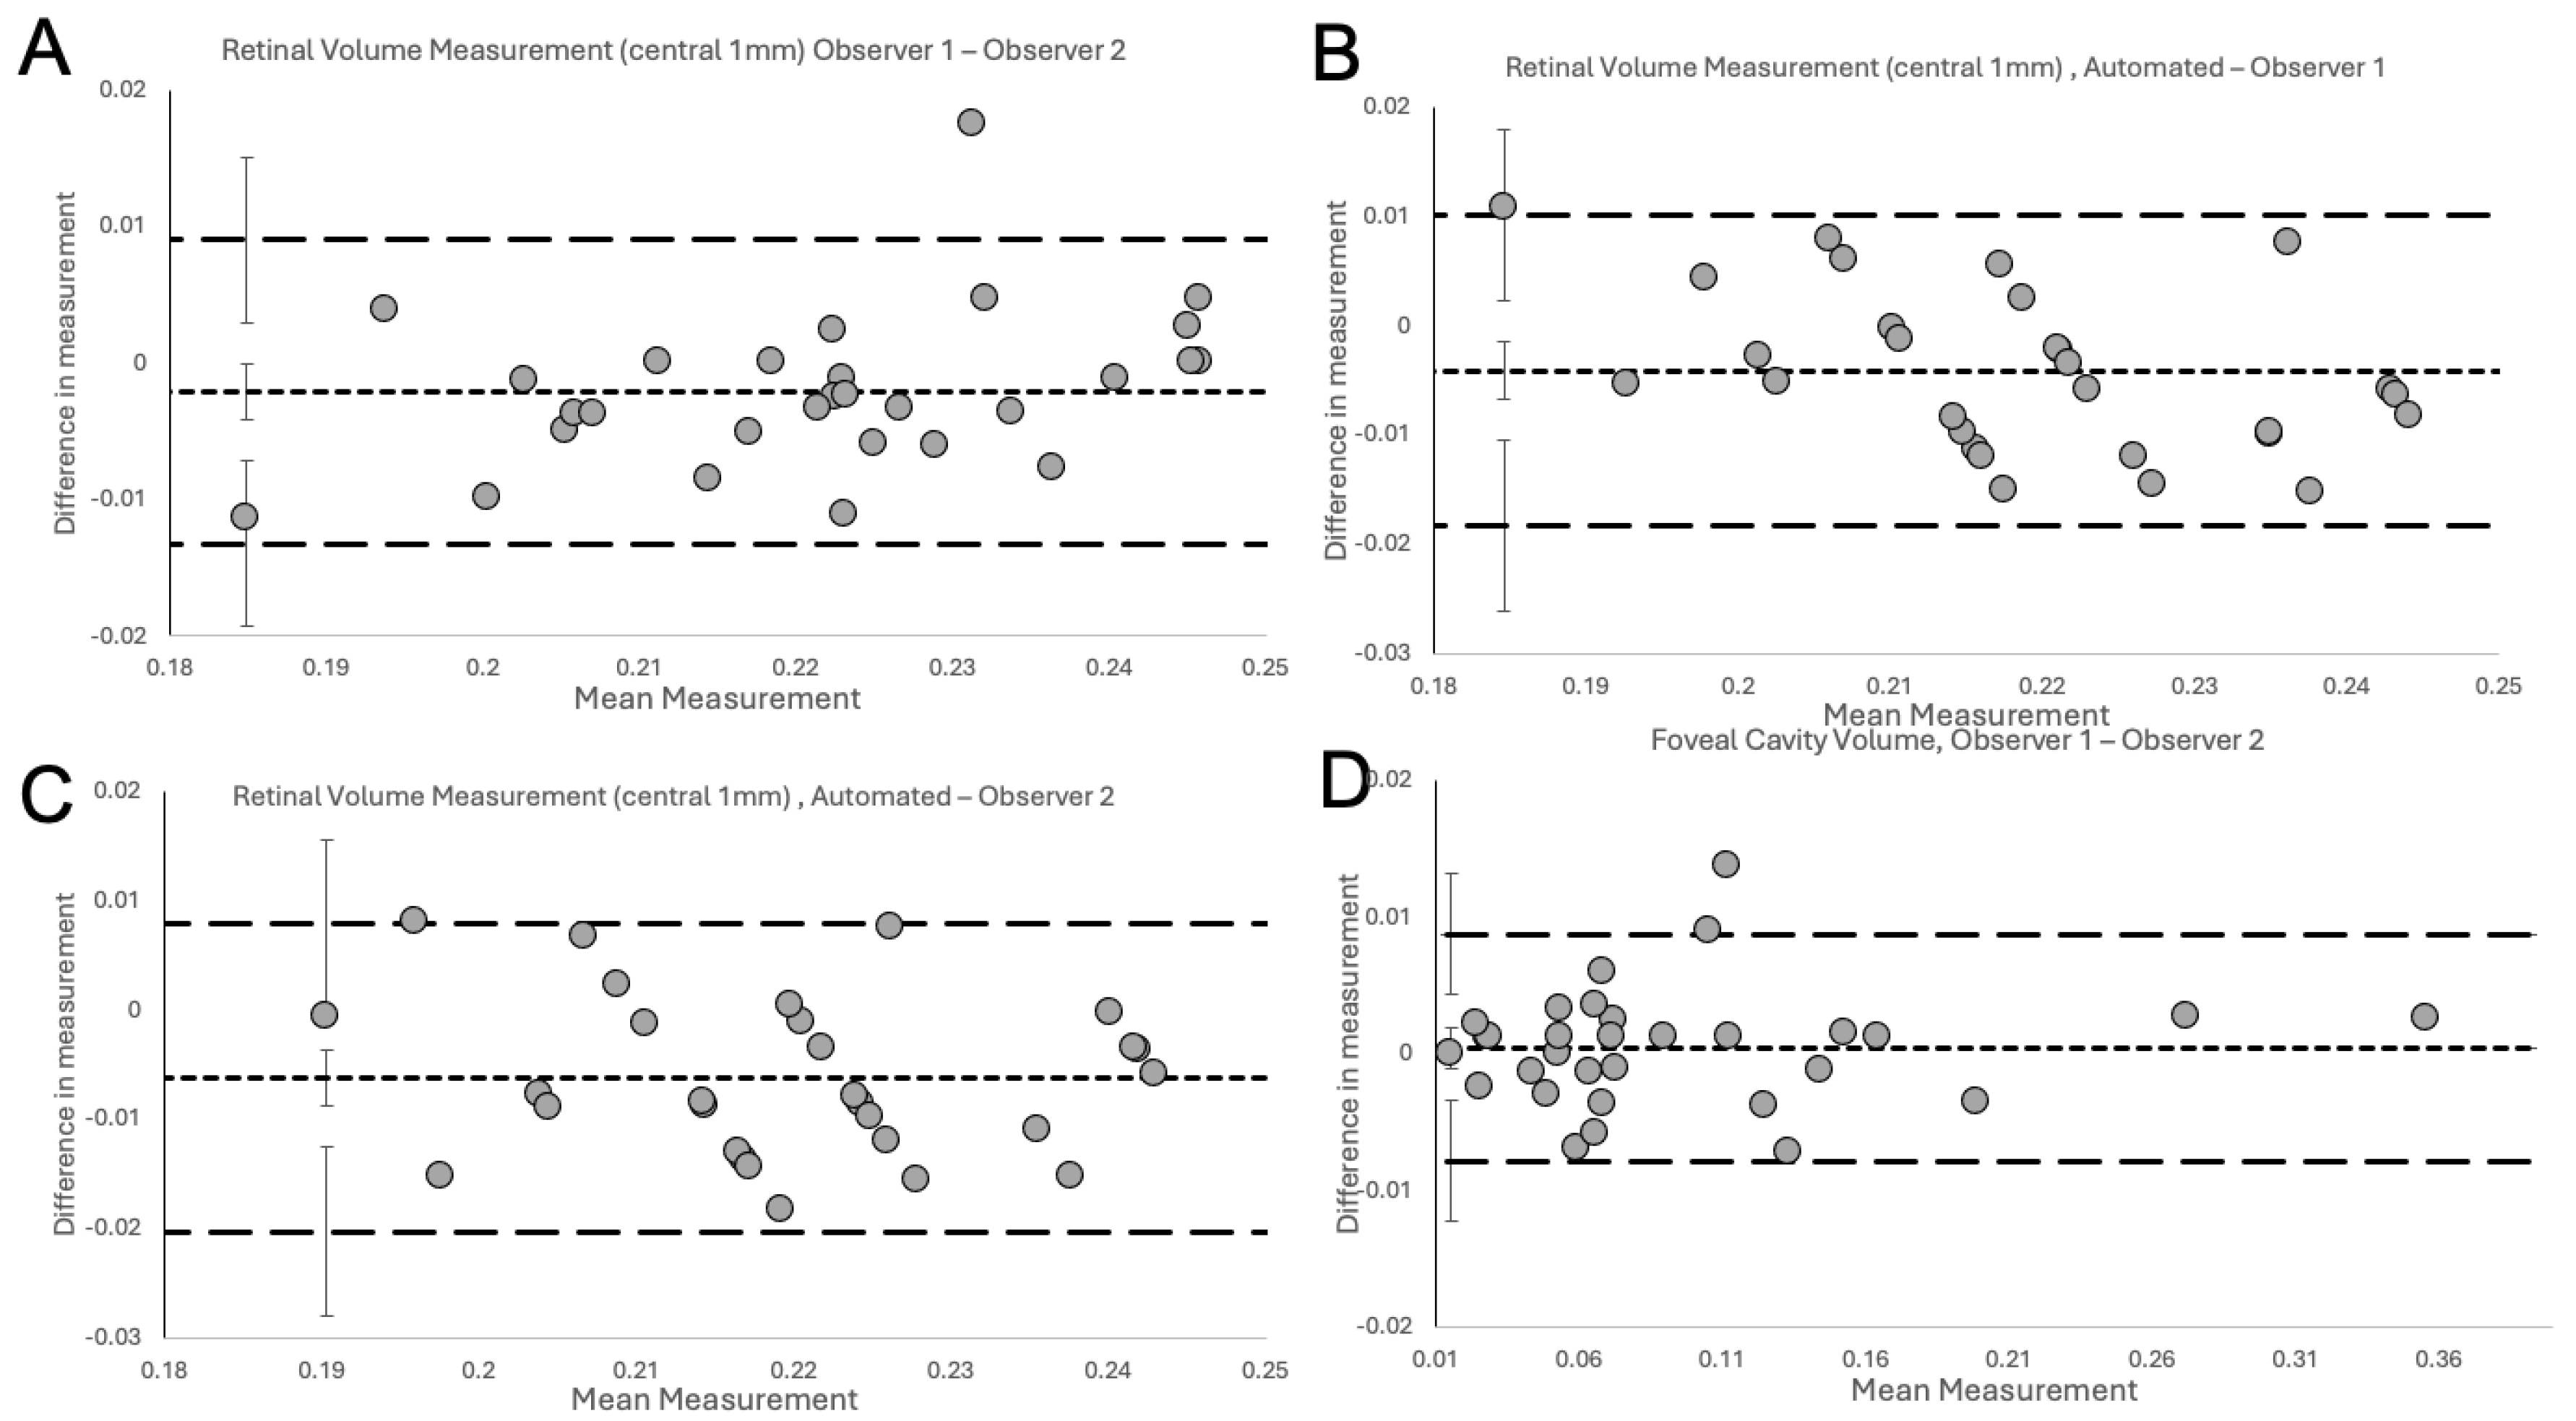

2.4. Statistical Analysis

3. Results

| Type of Comparison | n | Estimate of Bias (mm) | 95% CI (mm) | Lower Limit of Agreement (mm) | 95% CI (mm) | Upper Limit of Agreement (mm) | 95% CI (mm) | Coefficient of Repeatability (mm) |

|---|---|---|---|---|---|---|---|---|

| Intra-observer Total Retinal Volume | ||||||||

| Obs 1, Obs 1 | 30 | 0.0074 | 0.0048 to 0.0100 | −0.0067 | −0.0144 to 0.0010 | 0.0215 | 0.0138 to 0.0292 | 0.0141 |

| Obs 2, Obs 2 | 30 | 0.0066 | 0.0042 to 0.0090 | −0.0066 | −0.0139 to 0.0006 | 0.0198 | 0.0125 to 0.0270 | 0.0132 |

| Inter-observer Total Retinal Volume | ||||||||

| Obs 1-Obs 2 | 30 | −0.0021 | −0.0041 to −0.0001 | −0.0132 | −0.0193 to −0.0071 | 0.0090 | 0.0029 to 0.0151 | 0.0111 |

| Automated-Obs 1 | 30 | −0.0041 | −0.0067 to −0.0015 | −0.0184 | −0.0262 to −0.0106 | 0.0102 | 0.0024 to 0.0180 | 0.0143 |

| Automated-Obs 2 | 30 | −0.0062 | −0.0088 to −0.0036 | −0.0203 | −0.0280 to −0.0126 | 0.0079 | 0.0002 to 0.0156 | 0.0141 |

| Intra-observer Foveal Cavity | ||||||||

| Obs 1, Obs 1 | 32 | −0.0021 | −0.0061 to 0.0020 | −0.0242 | −0.0359 to −0.0125 | 0.0201 | 0.0083 to 0.0318 | 0.0221 |

| Obs 2, Obs 2 | 32 | −0.0048 | −0.0080 to −0.0016 | −0.0222 | −0.0315 to −0.0130 | 0.0126 | 0.0034 to 0.0219 | 0.0174 |

| Inter-observer Foveal Cavity | ||||||||

| Obs 1, Obs 2 | 32 | −0.0004 | −0.0020 to 0.0011 | −0.0088 | −0.0132 to −0.0043 | 0.0079 | 0.0035 to 0.0123 | 0.0083 |